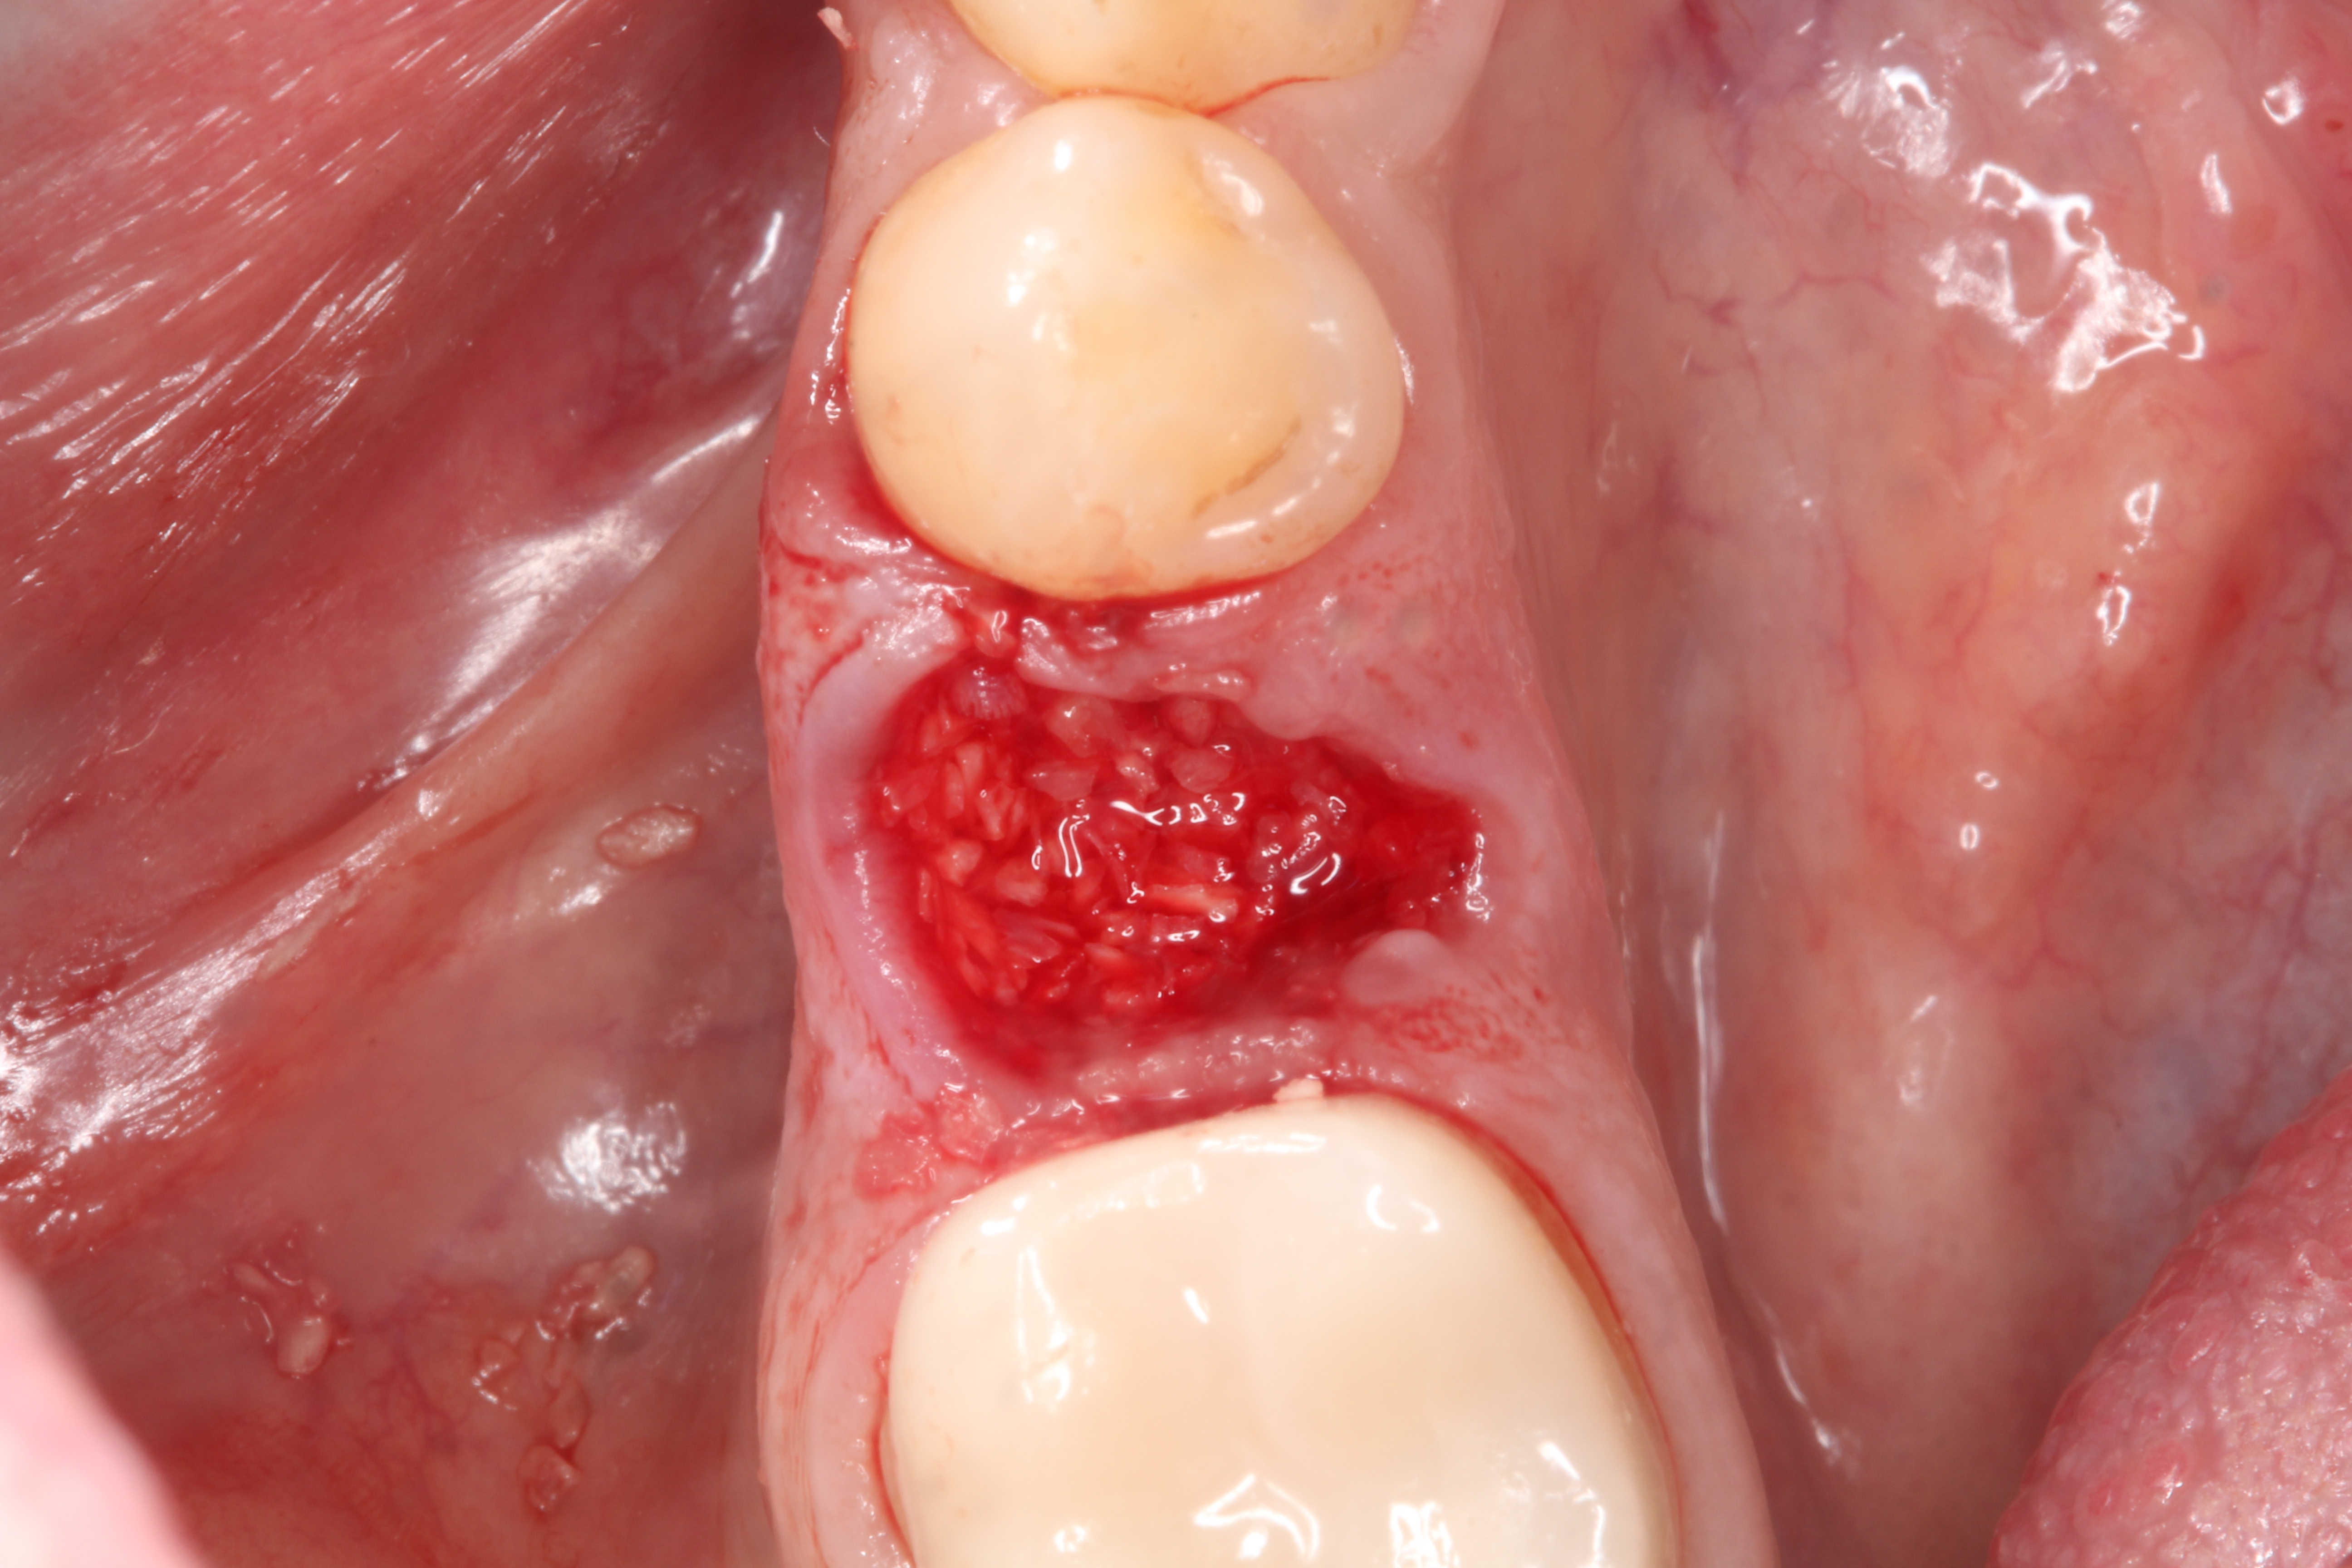

3. Make sure the socket is bleeding (Figure 6). If necessary, decorticate the remaining socket walls, using a round bur or surgical-type bur, to create a bleeding wound that will facilitate early vascularization and the beginning of the primary healing cascade.

Fig 6.The socket must be bleeding before delivering the graft material. This facilitates the healing cascade and greatly increases the success of the socket preservation.

Figure 6